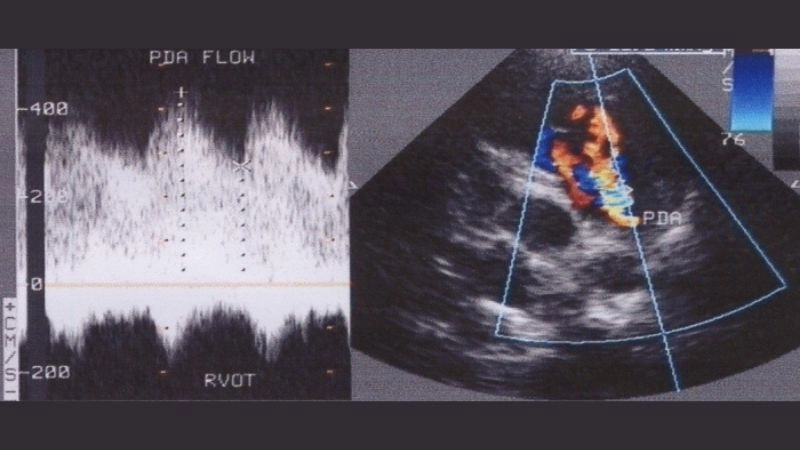

Images visual examples of Patent Ductus Arteriosus (PDA)

Patent Ductus Arteriosus is a congenital heart defect where a blood vessel connecting the pulmonary artery and aorta fails to close after birth, leading to abnormal circulation.